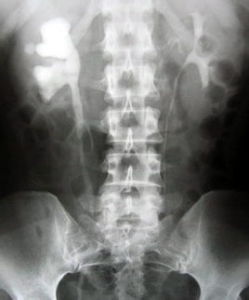

2、拍腹部平片:這是診治尿路結石最有價值的檢查,大約有95%的結石患者能在X線片上顯影。必要時進一步做靜脈腎盂造影,以了解腎功能和腎積水情況;

(三)X線檢查:X線檢查是診斷腎及輸尿管結石的重要方法,約95%以上的尿路結石可在X線平片上顯影。輔以排泄性或逆行性腎盂輸尿管造影,可確定結石的部位、有無梗阻及梗阻程度、對側腎功能是否良好、區別來自尿路以外的鈣化陰影、排除上尿路的其它病變、確定治療方案以及治療後結石部位、大小及數目的對比等都有重要價值。密度低或透光懷石,加以輸尿管、腎盂充氣造影,結石則顯示更為清晰。